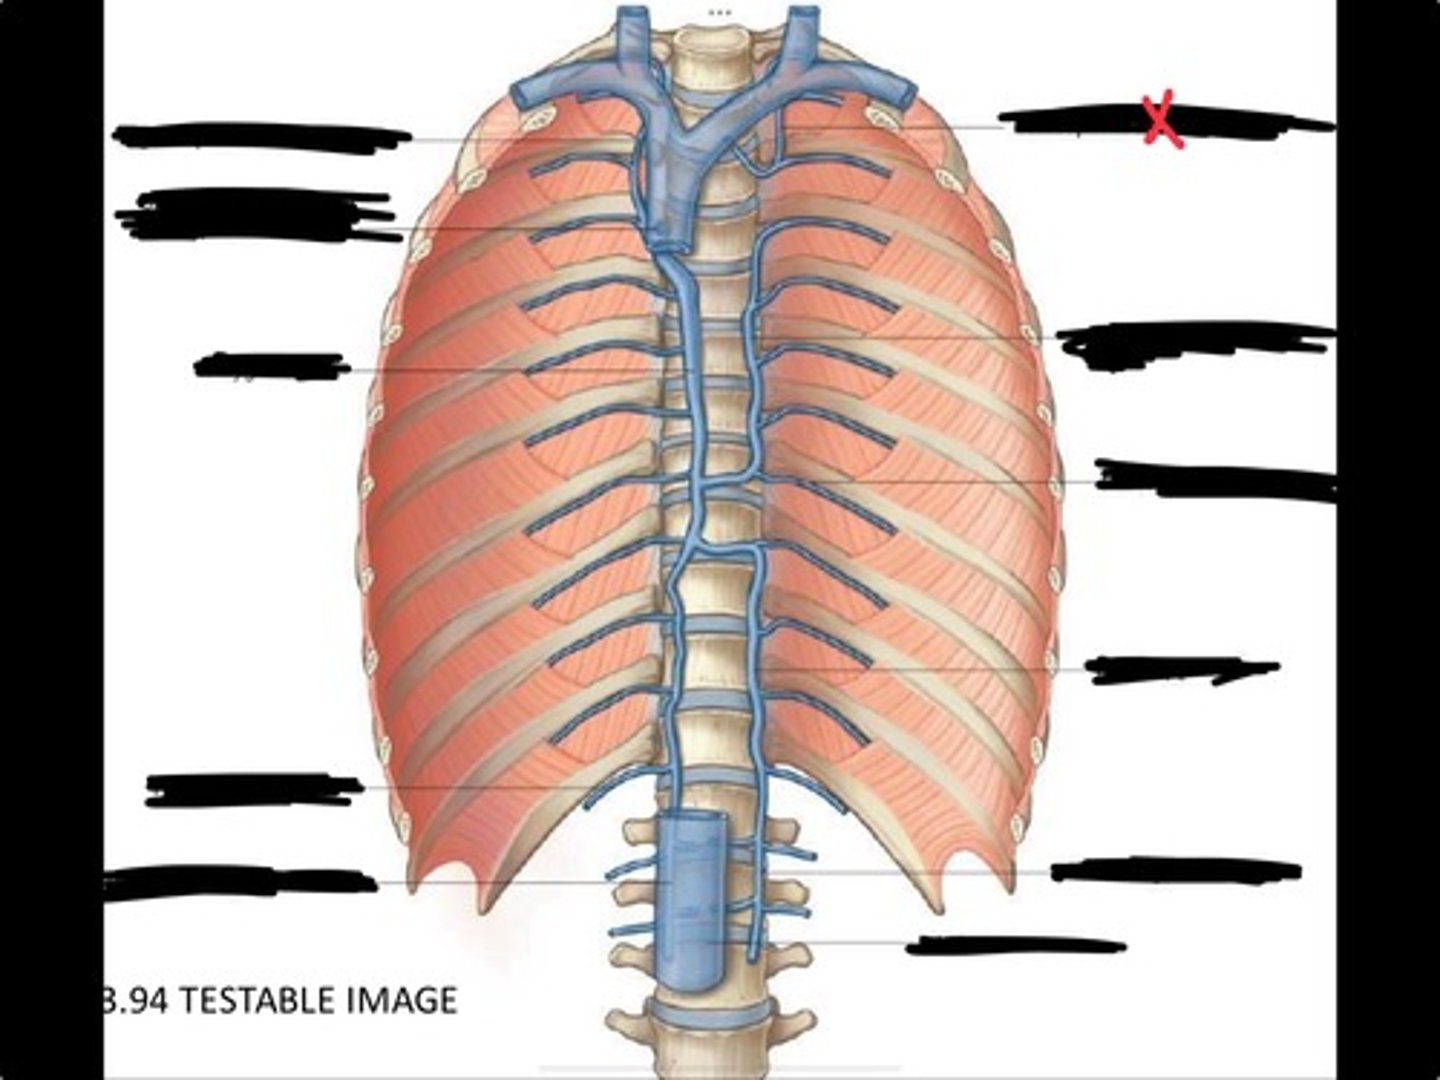

Right ascending lumbar vein

Right subcostal vein

Azygos vein

Opening of the azygos vein into superior vena cava

Right superior intercostal vein

Left superior intercostal vein

Accessory hemiazygos vein

Posterior intercostal vein

Hemiazygous vein

Ascending lumbar vein